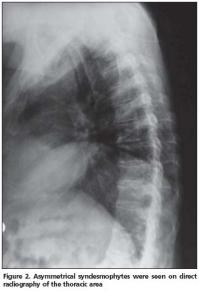

Anterior longitudinal ligament calcification, fusion of multiple facet joints and atypical syndesmophytes were found on cervical spine X-rays (Figure 1) and coarse, asymmetrical syndesmophytes were seen on thoracic (Figure 2) and lumbar spine (Figure 3) X-rays. No abnormalities suggesting PsA or gout were seen on hand and foot radiographs. The magnetic resonance imaging (MRI) of the sacroiliac joint and computerized tomography (CT) of atlanto-axial joint were normal.